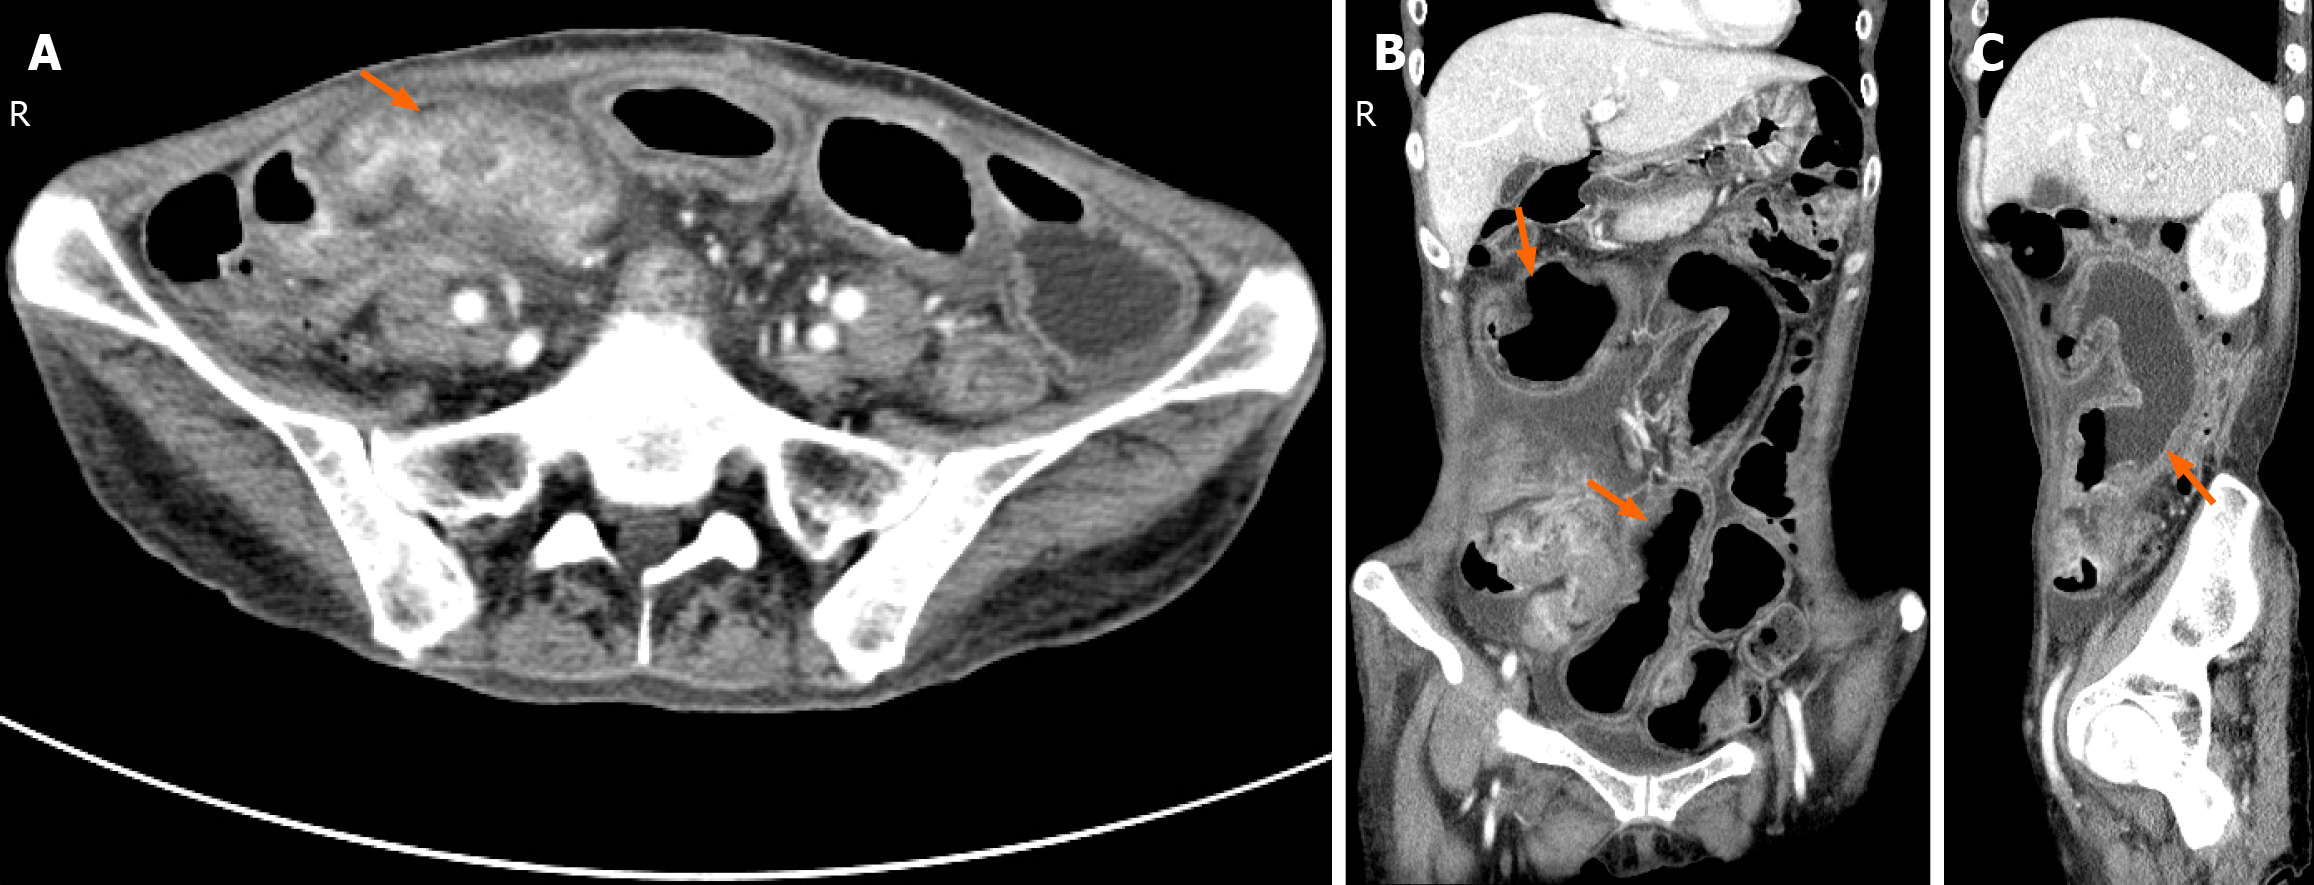

Figure 2 Abdominal enhanced computed tomography image.

A: Horizontal plane, Thickening of the intestinal wall of the terminal ileum, narrowing of the lumen, localized peritoneal thickening and accumulation of intestinal tubes, and enhancement of the intestinal wall (arrow); B: Coronal plane; C: Right sagittal plane, Proximal small bowel dilation, multiple bowel wall thickening and layered enhancement (arrows).